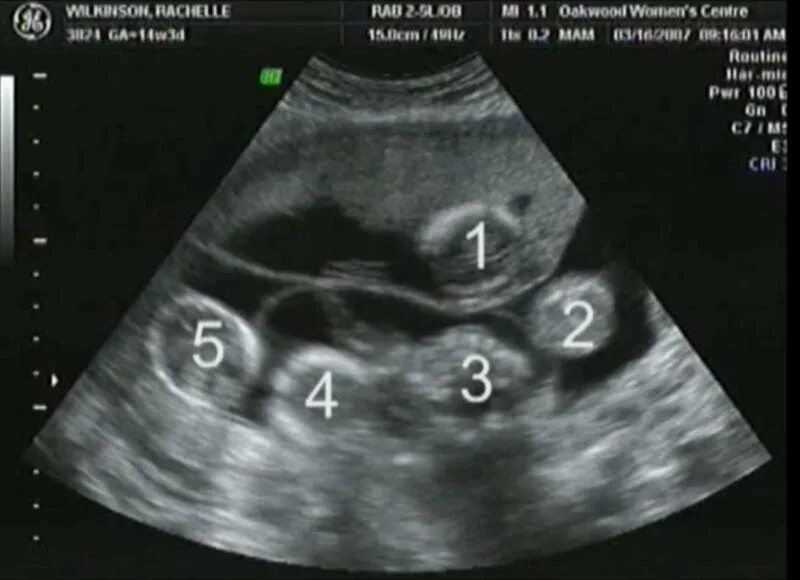

На каком сроке можно увидеть двойню